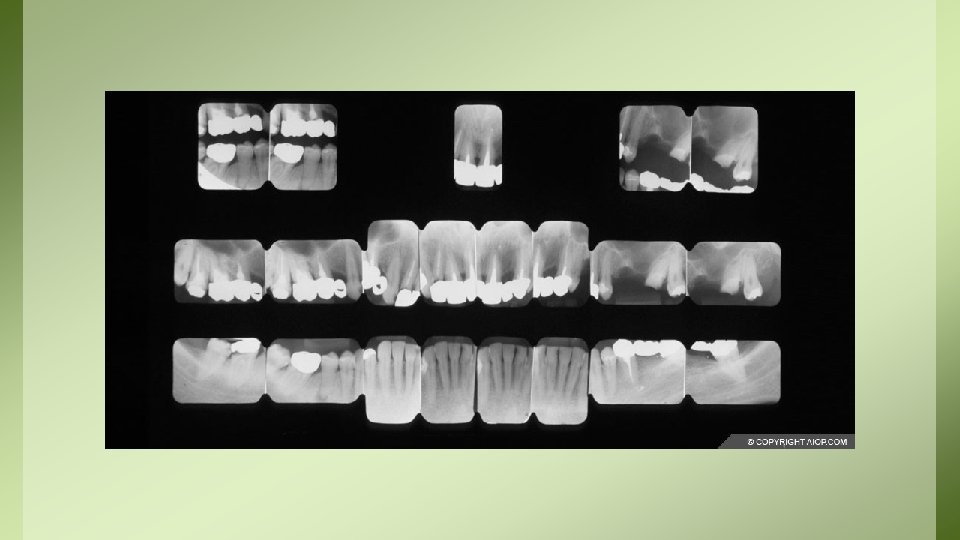

Documentazione Radiologica Sul tema della conservazione della documentazione di diagnostica per immagini, il D. M. del 14 febbraio 1997 (9)distingue: • a) documenti radiologici e di medicina nucleare, definiti come la “documentazione iconografica prodotta a seguito dell’indagine diagnostica utilizzata dal medico specialista nonché… quella prodotta nell’ambito delle attività radiodiagnostiche complementari all’esercizio clinico”; • b) resoconti radiologici e di medicina nucleare, cioè i “referti stilati dal medico specialista radiologo o medico nucleare”.

• La documentazione radiologica di cui al punto a) deve essere conservata (su pellicola radiografica, supporto cartaceo o elettronico) per un periodo NON inferiore ai 10 anni, ed essere resa disponibile e/o consegnata su richiesta al paziente o agli aventi diritto. – NOTA: per le CBTC deve essere assicurata adeguata archiviazione e conservazione del consenso informato per un periodo di almeno 5 anni e di tutte le immagini per non meno di 5 anni (come da raccomandazioni ministeriali del 2010) • La documentazione radiologica di cui al punto b) va invece conservata illimitatamente.